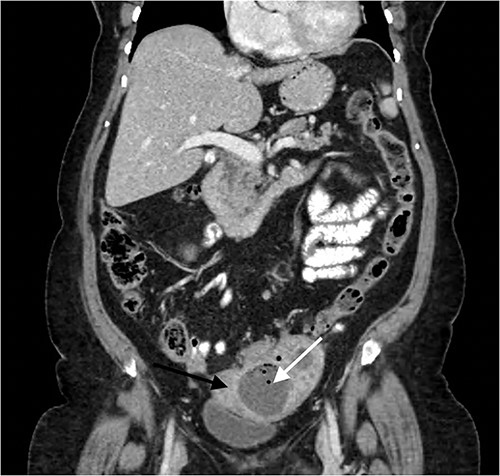

A 68-year-old woman presented to hospital with 1 month history of Left iliac fossa (LIF) pain and weight loss of 5 kg. She denied per vaginal (PV) discharge and urinary symptoms, and had no medical background nor a history of previous colonoscopies. On examination, she was haemodynamically stable, not in respiratory distress and was afebrile at 36.8°C. The patient demonstrated LIF tenderness but was not peritonitc. Laboratory results were significant for increased C-reactive Protein (CRP) of 185 mg/L, with normal white cell count (WCC) and normal tumour markers. Contrast enhanced computed tomography (CT) Abdomen/Pelvis, illustrated in Fig. 1, demonstrated a LIF mass measuring 3.9 cm × 3.4 cm × 2.9 cm in the area of the left ovary, abutting the sigmoid colon, containing both solid and cystic components, with appearances inconclusive for ovarian neoplasia or pericolic abscess. There was evidence of sigmoid diverticulosis without diverticulitis.

Contrast enhanced CT Abdomen/Pelvis demonstrating mixed cystic/solid LIF mass (white arrow) adherent to the sigmoid colon and uterus (black arrow).